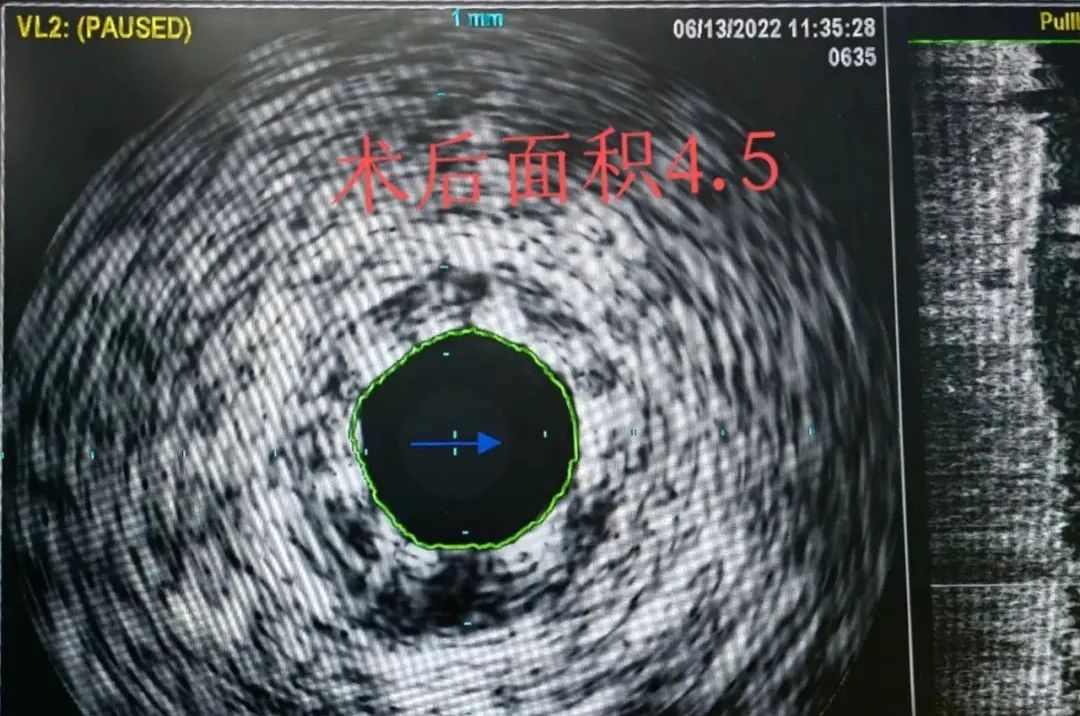

一直以來,冠狀動(dòng)脈造影是公認(rèn)的冠心病診斷的“金標(biāo)準(zhǔn)”,但冠脈血管內(nèi)超聲(IVUS)是在傳統(tǒng)的冠脈造影基礎(chǔ)上,把微型化的超聲探頭置于導(dǎo)管頭端,置入冠脈血管腔內(nèi)進(jìn)行顯影,可提供包括管腔和管壁在內(nèi)的橫截面圖像。它好似介入醫(yī)生的“眼睛”,可以幫助我們看清血管內(nèi)部的結(jié)構(gòu),更好為術(shù)者提供臨床指導(dǎo),指導(dǎo)我們有效合理的運(yùn)用支架,并在即時(shí)評估支架效果以及支架預(yù)后評估中都起到了不可替代的作用。

6.確定網(wǎng)狀支架的位置及擴(kuò)張效果;

冠脈血管內(nèi)超聲(IVUS)的成功應(yīng)用,填補(bǔ)了我院在冠心病的介入輔助腔內(nèi)影像學(xué)領(lǐng)域的空白,極大地豐富了冠脈介入治療的手段,讓鄭州市高新區(qū)及周邊廣大居民在家門口享受到快捷、高效、低成本的優(yōu)質(zhì)醫(yī)療服務(wù)。